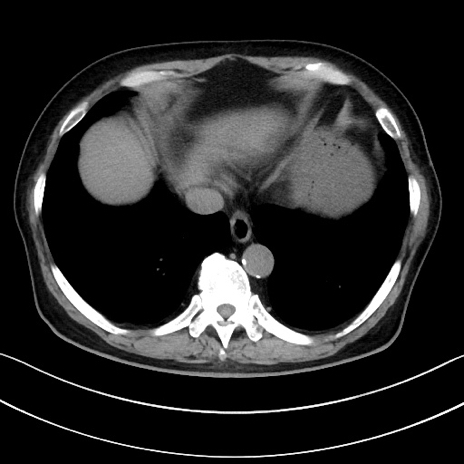

症例15(横断像)

【症例】70歳代男性

【主訴】腹痛

【現病歴】今朝から腹痛あり。全体的に痛い。特に左上の方。排ガスが今日はない。冷や汗が出る。

【既往歴】直腸癌術後

【身体所見】左側腹部〜上腹部に圧痛あり。腹膜刺激症状明らかなではない。軽度反跳痛。左下腹部に術後瘢痕あり。

【データ】WBC 7700、CRP 0.02